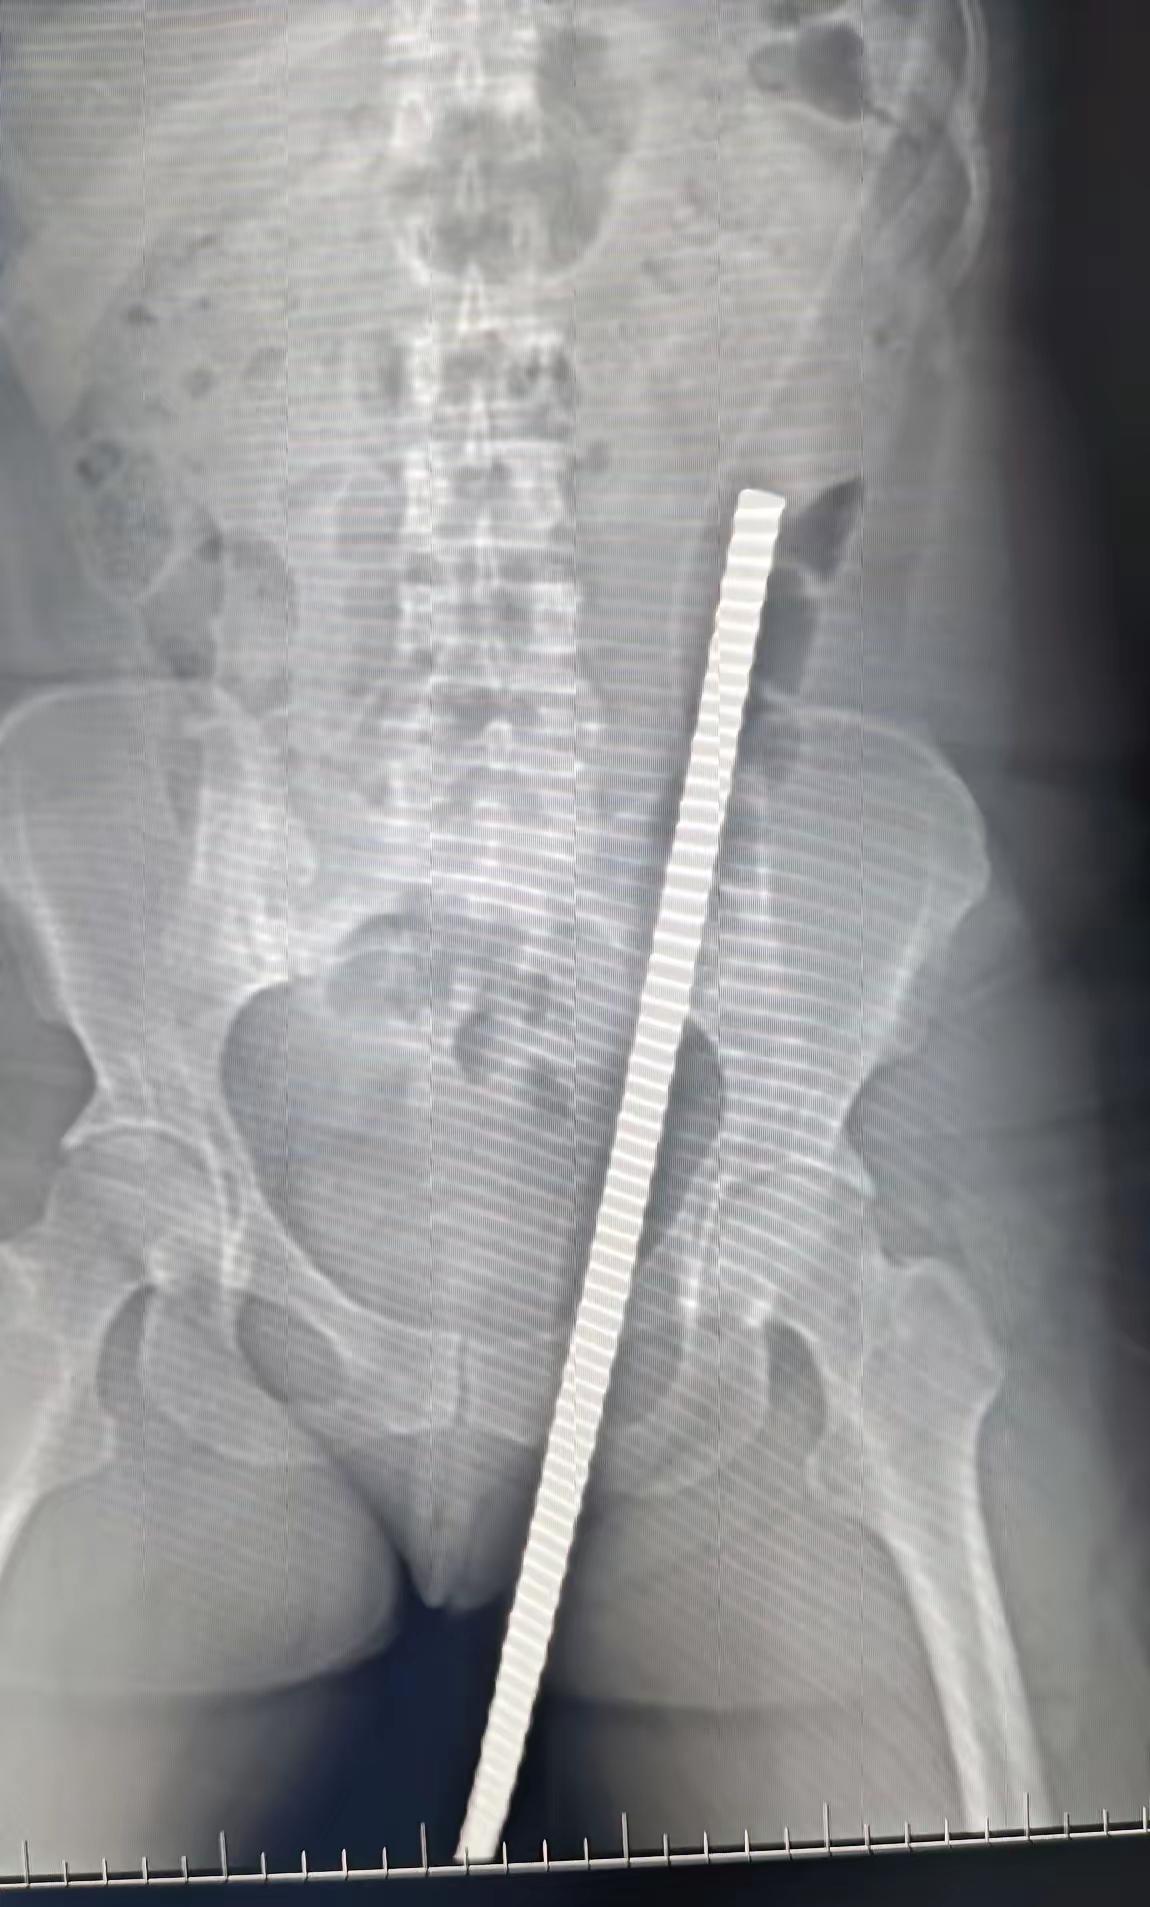

女性,47岁,工地干活,从楼梯上摔下,钢筋穿入会阴部,从皮肤穿出,不幸中的幸运,